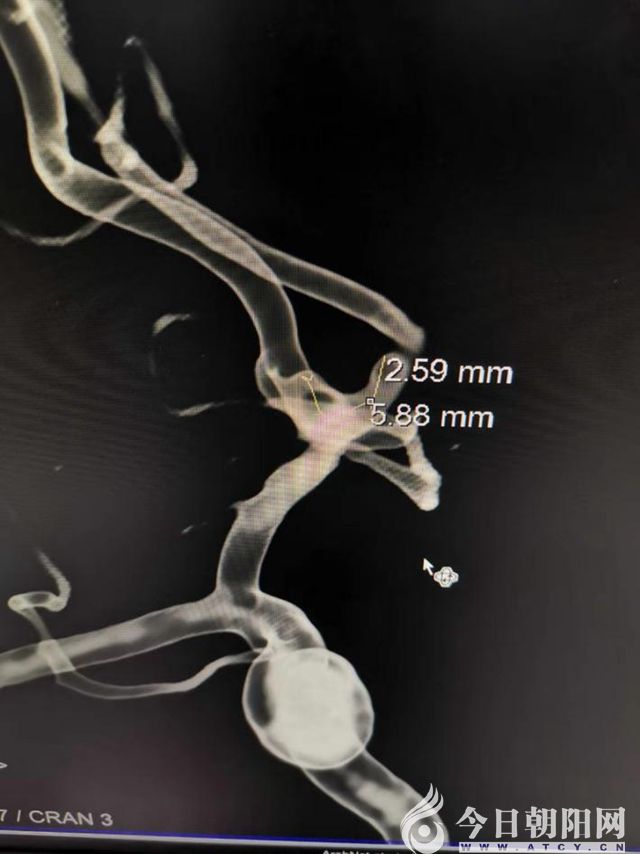

3D—DSA成像

3D—DSA成像內(nèi)徑測量